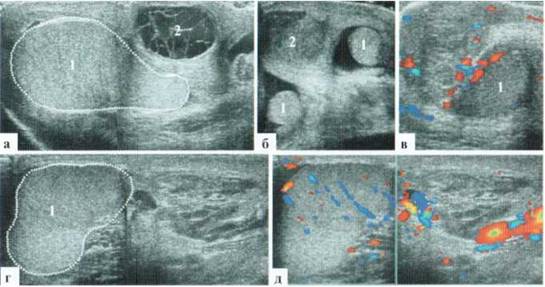

Антенатальный перекрут

Причина и точные сроки возникновения антенатального перекрута яичка у младенцев до настоящего времени не известны. В литературе имеются описания дородовой ультразвуковой диагностики перекрута яичка у плода с послеродовым интраоперационным подтверждением. В практической деятельности большинство новорожденных с антенатальным перекрутом яичка переводятся в профильное отделение на 2—3 сутки жизни, при этом дооперационное УЗИ выявляет грубые структурные изменения тестикул и отсутствие сосудистого рисунка в ткани яичка, что не оставляет надежд на благоприятный исход (рис. 2.6.I2).

Рис. 2.6.12. Антенатальный перекрут и некроз яичка: а, б — яичко плохо дифференцируется от окружающих тканей, бесструктурное, в оболочках определяется немного гетерогенного содержимого, сосудистый рисунок в паренхиме яичка не прослеживается; в, г — на операции: перекрут яичка, на разрезе яичко черное

При консервативной тактике ведения таких пациентов яичко постепенно склерозируется, при этом оно значительно уменьшается в размерах, в возрасте 2—3 месяцев едва достигает 6x5мм, паренхима его остается бесструктурной и аваскулярной (рис. 2.6.13).

Рис. 2.6.13. Исход антенатального перекрута яичка: а — на 2-е сутки жизни яичко размерами около 14x6 мм, неправильной формы, бесструктурное, аваскулярное, дифференцируется с трудом; б, в — в возрасте 2.5 месяцев яичко 6x4 мм, склерозировано

Казуистически редким является перекрут обоих яичек. Прогноз для ребенка в плане нарушения гормонального статуса и дифференцировки вторичных половых признаков серьезный (рис. 2.6.14).

Рис. 2.6.14. Антенатальный перекрут и некроз обоих яичек: а, б — поперечный скан мошонки. Оба яичка плохо дифференцируются от окружающих тканей, структура яичек гетерогенная, четко проследить контуры яичек невозможно, сосудистый рисунок прослеживается только в оболочках яичек; в, г — правое яичко; д, е — левое яичко

После перенесенного 2-стороннего антенатального перекрута яичек также развивается их склероз с типичными изменениями тестикулярных структур с обеих сторон (рис. 2.6.15)

Рис. 2.6.15. Ребенок 2 месяцев, состояние после 2-стороннего антенатального перекрута яичек. Оба яичка значительно уменьшены в размерах, определяется типичное повышение эхогснности поверхностного слоя паренхимы яичек